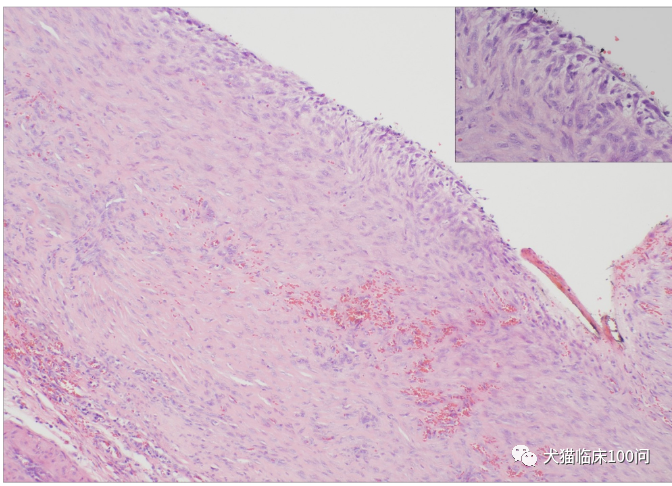

全腹超声检查显示慢性肾病和囊性前列腺增生,但充满液体的肿物和腹部无关。前列腺冲洗样本未检测到细胞学异常或BARF突变,与临床医生进一步讨论表明,病变实际可还原,临床诊断为会阴疝。采用经典疝修补术并辅以闭孔内肌移位术修补缺损。切除组织进行组织病理学检查发现脂肪组织有明显的纤维增生、轻度间皮肥大,和多灶性新发淋巴滤泡形成,结果与包裹的腹膜脂肪组织一致,这些组织已经发生纤维化,最终诊断为会阴疝(图3)